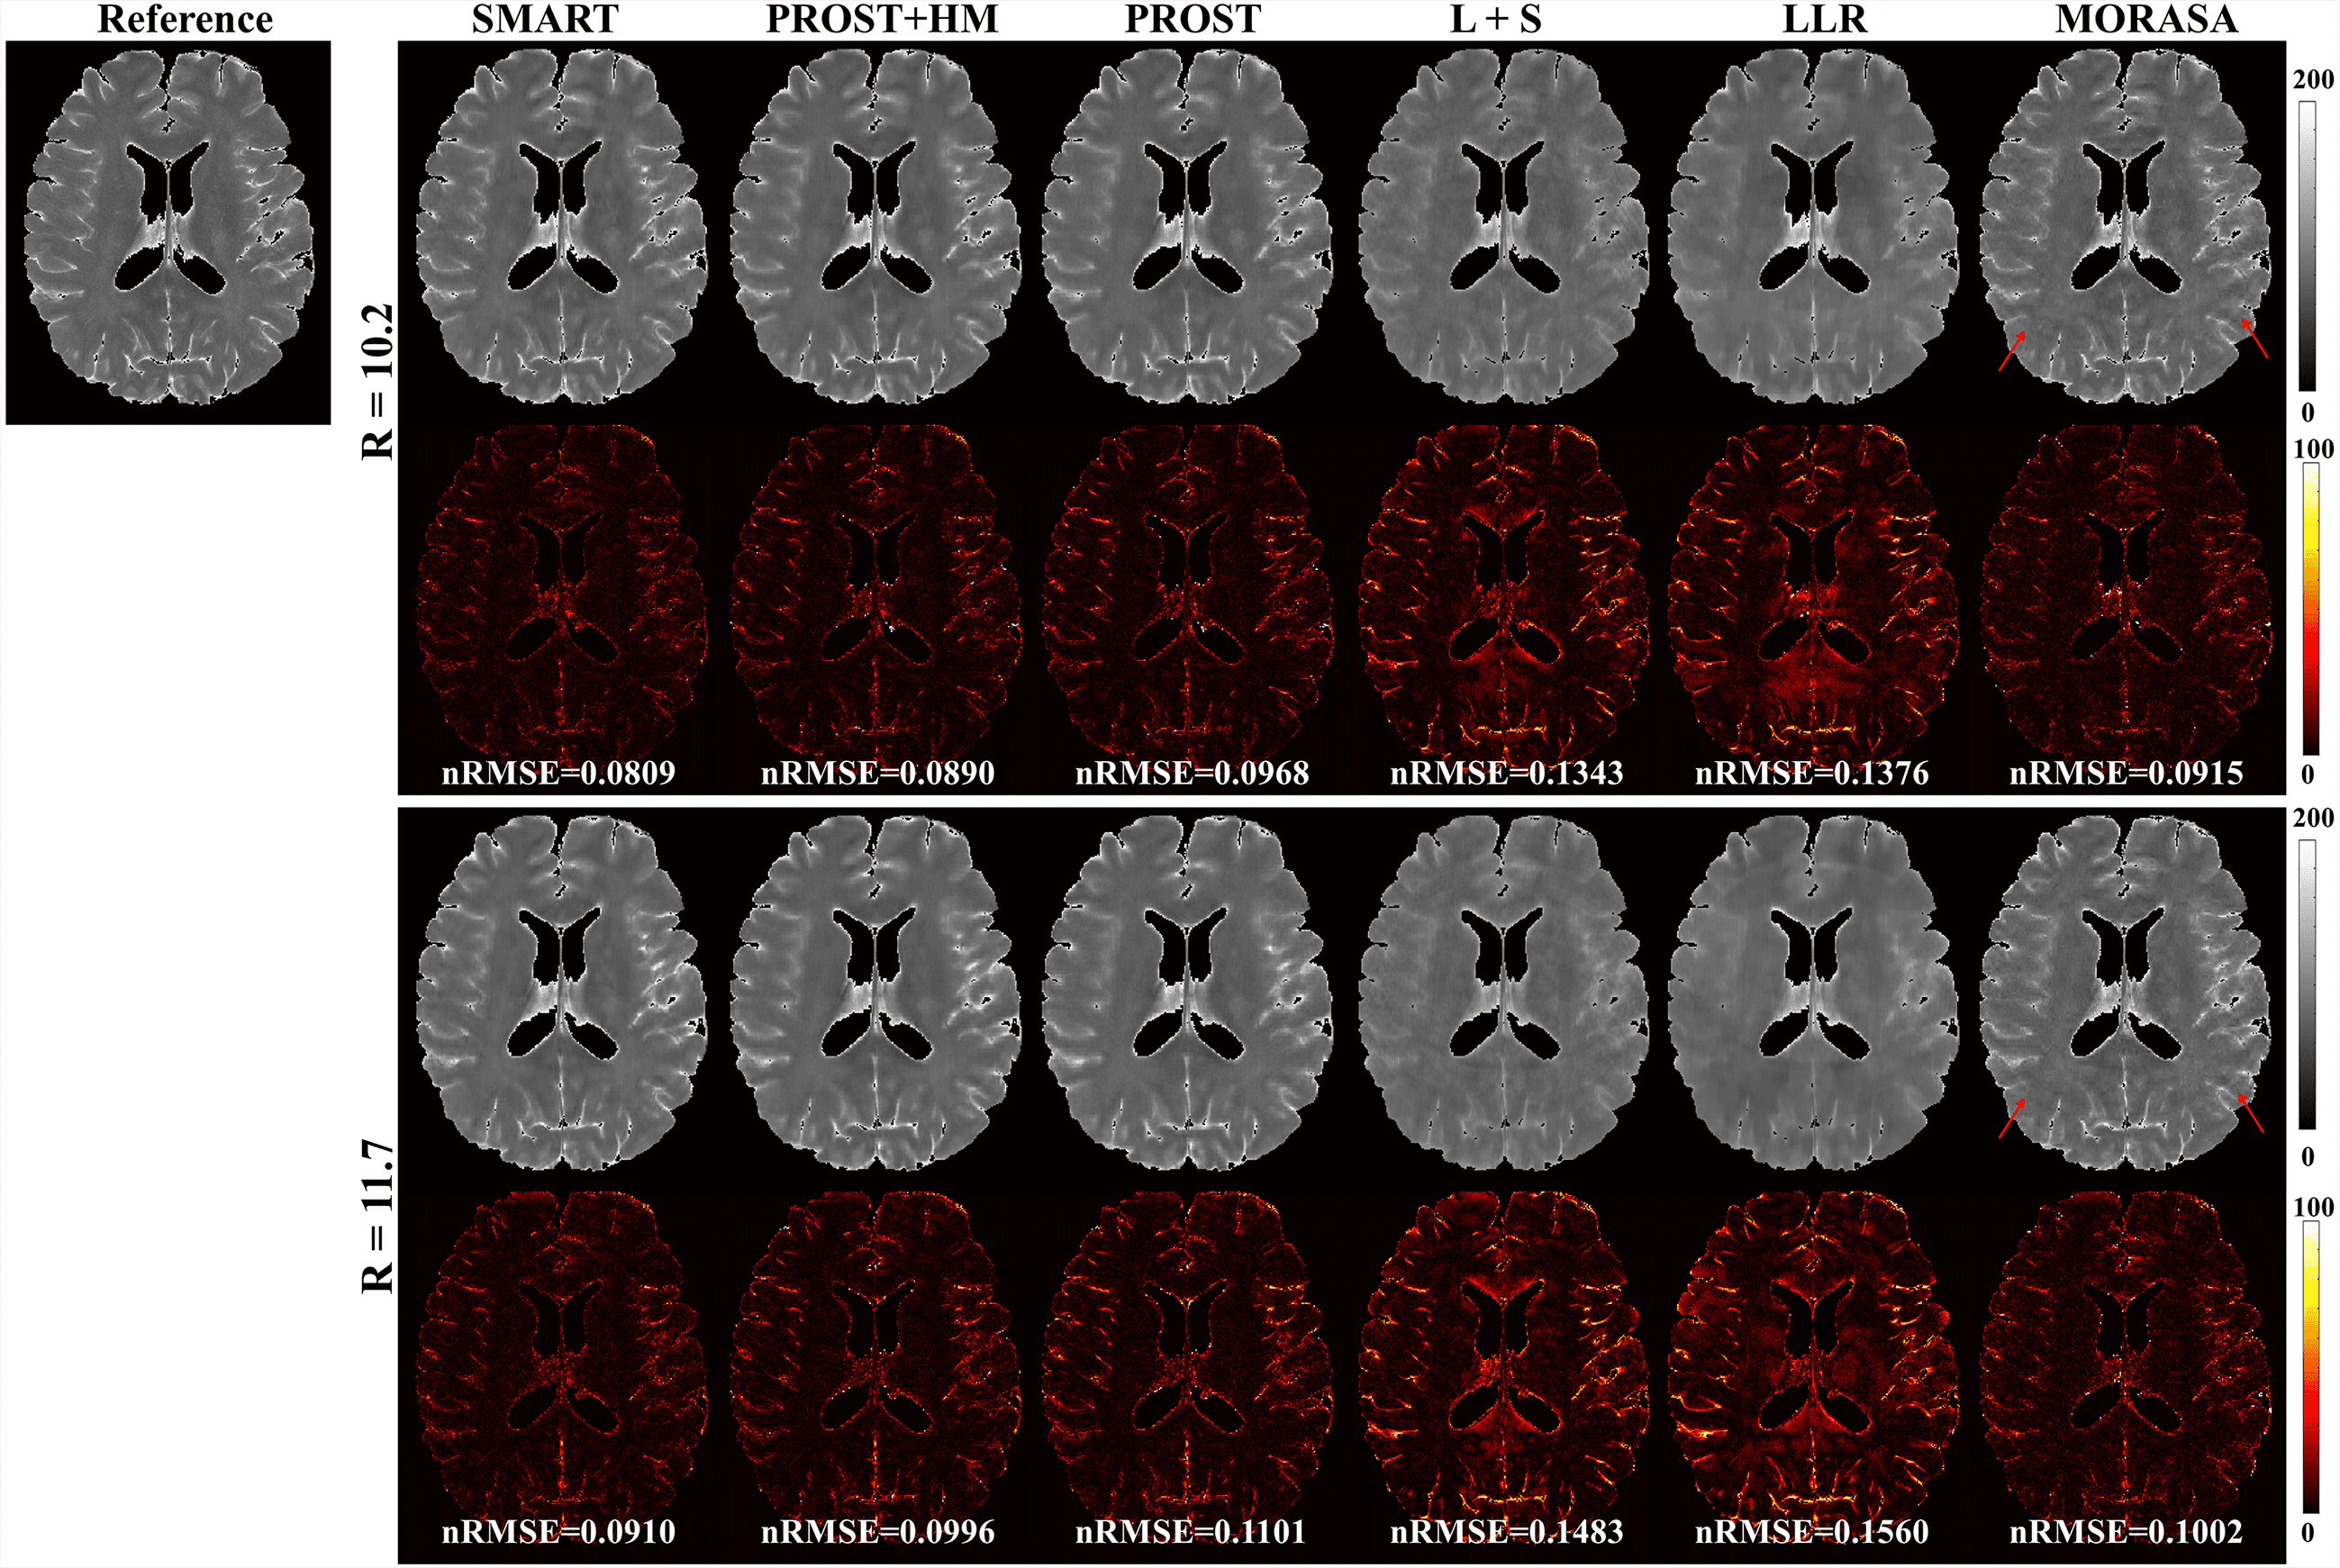

4.2.2 Higher acceleration with 10.2-Fold and 11.7-Fold

The reconstructed -weighted images and the corresponding error images with R = 10.2 and 11.7 are shown in Fig. 5. The nRMSEs are shown at the bottom of each error image. The reconstructed -weighted images using the SMART method have no notable artifacts, even at a high acceleration factor of up to 11.7. The related errors remain noise-like, and the nRMSEs are less than 3. Noticeable aliasing artifacts can be observed from the images or error maps using the PROST+HM, PROST, L+S, LLR, and MORASA methods at different TSLs. The corresponding maps are shown in supplementary information Fig. S3. Table 2 shows the average HFEN, SSIM, and PSNR values for all reconstructed -weighted images. The proposed SMART method qualitatively achieves the best performance among the six methods, especially at R = 11.7.

| Metrics | SMART | PROST+HM | PROST | L+S | LLR | MORASA | |

|---|---|---|---|---|---|---|---|

| 10.2 | HFEN | 0.2558 | 0.2953 | 0.3360 | 0.4057 | 0.4369 | 0.3459 |

| SSIM | 0.9728 | 0.9688 | 0.9637 | 0.9582 | 0.9542 | 0.9674 | |

| PSNR | 40.3712 | 39.4523 | 38.5946 | 36.8233 | 35.3039 | 37.8079 | |

| 11.7 | HFEN | 0.2817 | 0.3460 | 0.4134 | 0.4527 | 0.5148 | 0.3762 |

| SSIM | 0.9701 | 0.9640 | 0.9578 | 0.9533 | 0.9472 | 0.9634 | |

| PSNR | 39.6822 | 38.1819 | 36.8288 | 35.9089 | 33.6896 | 37.2335 |